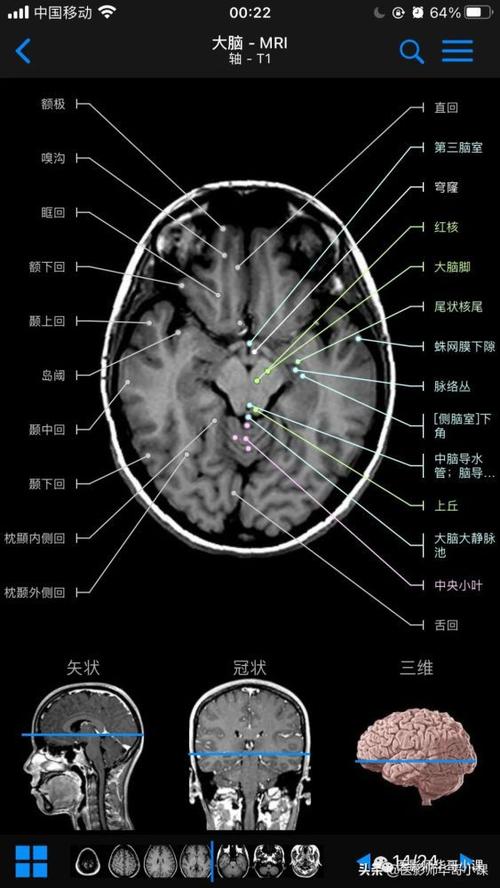

超详细头颅mr高清解剖(必点收藏)

高清mri图颅脑磁共振mri解剖